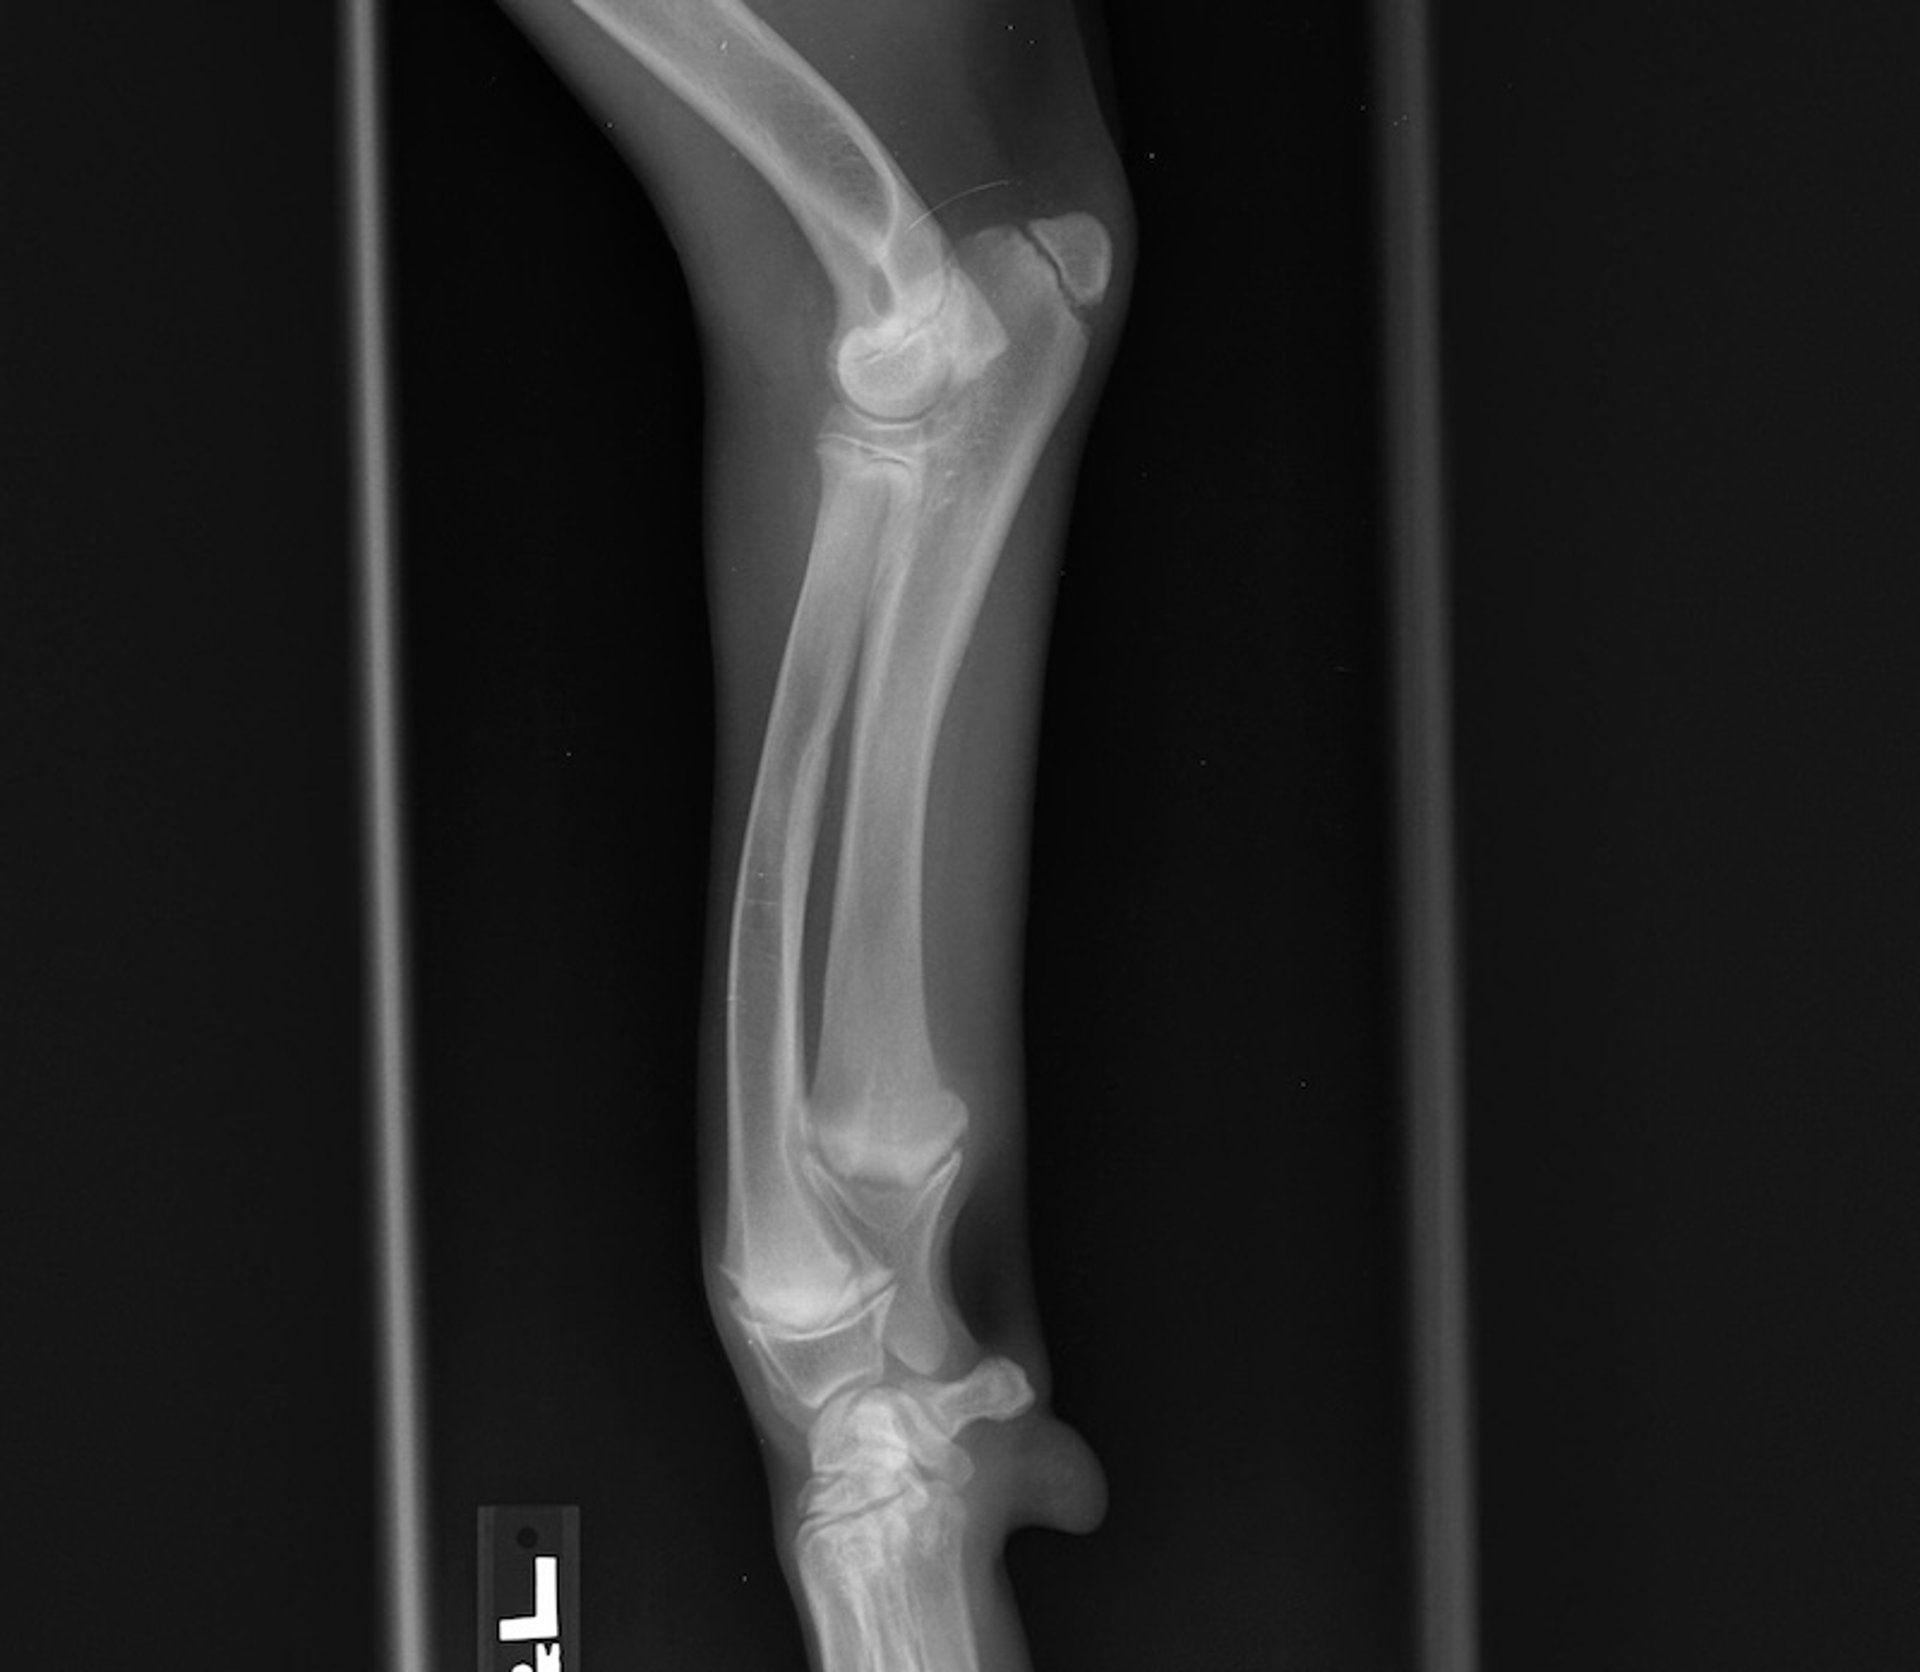

Angular Deformity of the Forelimb in Dogs and Cats

Angular limb deformity in dogs and cats is a condition characterized by abnormal spatial alignment of bones in a limb. This issue most commonly affects forelimbs, particularly the radius and ulna, and can arise because of asynchronous growth of paired bones, traumatic injury of the physis during development, or hereditary breed characteristics (eg, of Bulldogs, Pugs, Boston Terriers, Basset Hounds, Dachshunds).

The distal ulnar physis accounts for 80% of total ulnar growth and is the most common location for physeal injury. Asynchronous growth of the radius and ulna leads to shortened limbs, cranial bowing, torsion, and valgus or varus deformity of the radius and ulna, as well as to elbow joint or carpal joint subluxation.

Clinical signs of angular limb deformity include lameness and decreased, painful motion in the joints adjacent to the deformity, such as elbow or carpal joints for radius and ulna deformity.

Radiography reveals the bone deformations and premature closed physes. Nonfunctional physes can have a normal radiographic appearance; therefore, the presence of open physes does not rule out physeal damage (see ). CT scans provide additional information for complete evaluation of complex angular deformities.